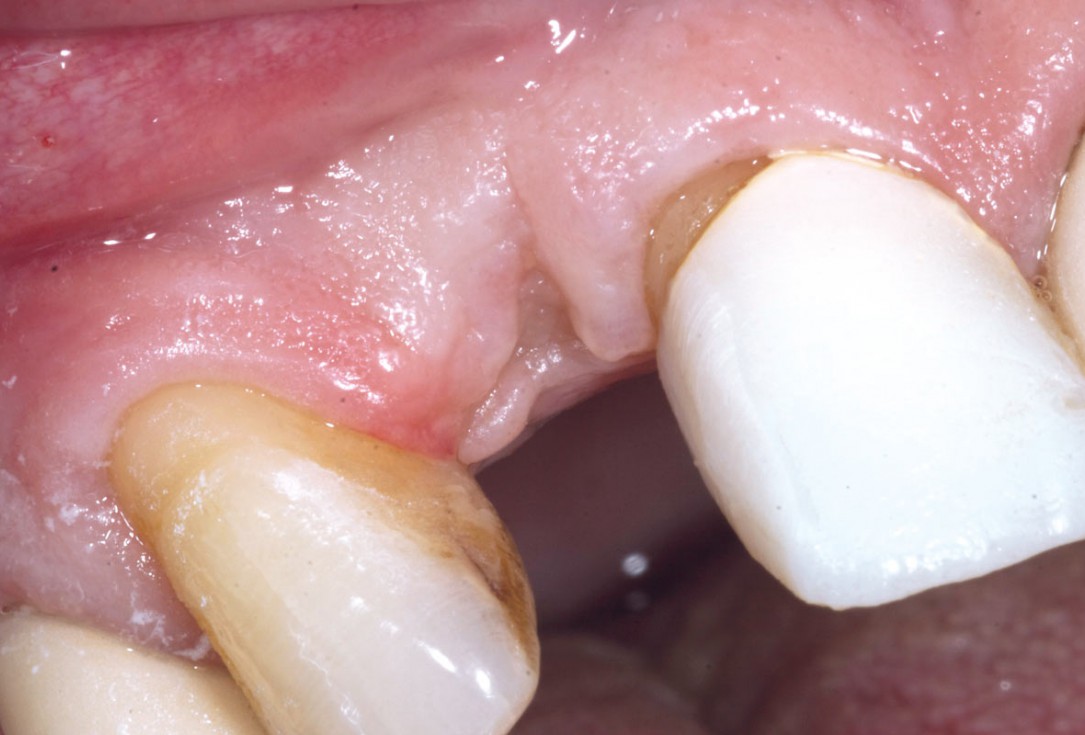

5/19 - 7 weeks after extraction of healing with a temporary tooth supported cantilever bridgeBone augementation with maxresorb® - Dr. R. Cutts

6/19 - Site without prosthetics showing sever buccal bone lossBone augementation with maxresorb® - Dr. R. Cutts